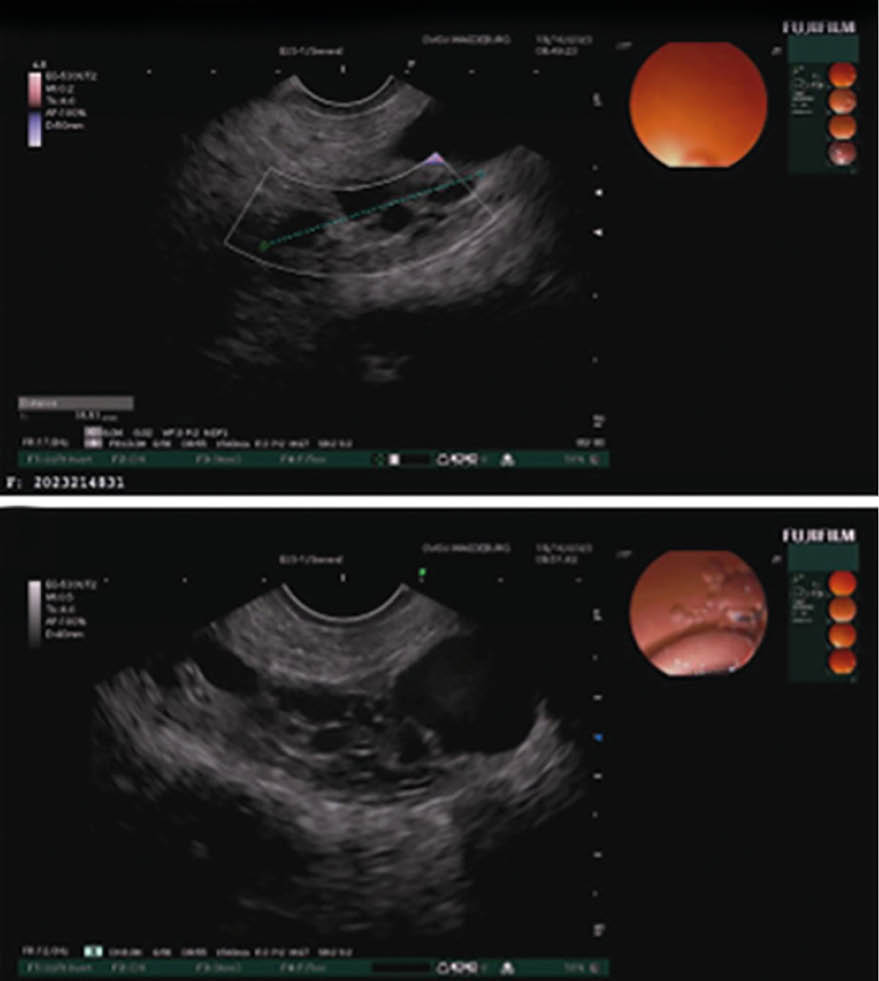

Muzinös-zystische Neoplasien (MCN) – Abb. 1.C & 2.A

MCN betreffen fast ausschließlich Frauen und wachsen in der Mehrzahl in Pankreaskorpus und -schwanz. Es zeigen sich in der Bildgebung dickwandige Einzelzysten mit Septen und teilweise wandständigen Knoten, die mit Muzin gefüllt sind und keinen Anschluss zum Pankreasgang haben. Ein MRT soll immer von einer Endosonographie (EUS) gefolgt werden, da 18 % der MCN inkorrekt diagnostiziert werden 9.

MCNs haben das Potenzial, sich zu bösartigen Erkrankungen zu entwickeln über die Adenom-Karzinom-Sequenz. In großen Serien konnte gezeigt werden, dass 11 % der resezierten MCN eine invasive Komponente haben. Für die Praxis gilt: MCN > 4 cm sollten reseziert werden. Auch bei MCN < 4 cm wird im Falle von klinischen Symptomen oder Vorliegen von soliden Anteilen die Resektion empfohlen, da diese entsprechende Risikofaktoren für eine bösar-tige Entartung darstellen. Kleine asymptomatische MCN sollten mittels MRT und/oder EUS beobachtet werden. Die Verlaufskontrollen sollten 6-monatlich im ersten Jahr und daraufhin jährlich durchgeführt werden 4,9.

Intraduktale papilläre muzinöse Neoplasien (IPMN) – Abb. 2.B/C & 3

IPMN sind muzinproduzierende zystische Strukturen mit Anbindung an das Pankreasgangsystem. Sie kommen in beiden Geschlechtern gleichermaßen vor, wobei die Inzidenz mit dem Alter steigt. IPMN sind die häufigsten zystischen Pankreasneoplasien und differenzieren sich je nach ihrer Lokalisation in Hauptgang-IPMN, Seitengang-IPMN und Mischtyp-IPMN. Hauptgang-IPMN und Mischtyp-IPMN zeigen in 34 – 39 % der Fälle ein invasives Wachstum und sollten daher chirurgisch reseziert werden 10,11.

Seitengang-IPMN unterscheiden sich stark von Hauptgang-IPMN hinsichtlich ihres Entartungspotenzials. Eine umfangreiche Meta-Analyse hat gezeigt, dass Seitengang-IPMN eine Malignitätsrate von 2,7 % aufweisen und daher nur unter bestimmten Kriterien einer Operation zugeführt werden sollten 12.

Wenn nach einer CT- und/oder MRT-Untersuchung keine eindeutige Diagnose vorliegt, sollte eine EUS durchgeführt werden. Obwohl diese Untersuchung stark von der Erfahrung des Untersuchers abhängt, ist sie hilfreich zur Unterscheidung zwischen muzinösen und nichtmuzinösen Zysten sowie zur Bewertung von worrisome features und high-risk stigmata (Tab. 1), die auf eine Malignität hinweisen können 18. Zur Beurteilung von randständigen Knoten ist die Kontrast-EUS die bevorzugte Technik. Falls weiterhin Zweifel bestehen, ist die Feinnadelaspiration (FNA) zur Analyse der Zystenflüssigkeit notwendig, sofern dies technisch machbar ist. Die Analyse der Zystenflüssigkeit kann zur Identifizierung des Zystentyps verwendet werden. Dabei sind erhöhte CEA-Werte bei muzin-produzierenden Zysten mit einer Genauigkeit von 79 % verbunden, während erhöhte Amylasewerte eine Spezifität von über 90 % für eine Pseudozyste aufweisen 19.